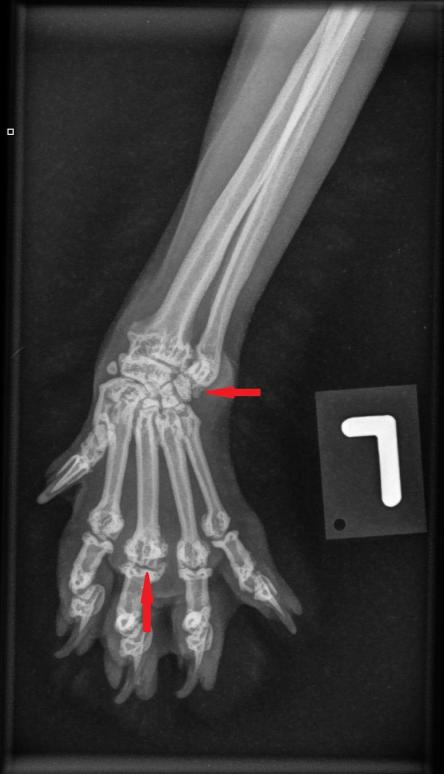

Die Besitzerin berichtet, dass der Kater recht lahmheitsfrei laufe, aber nicht über eine grosse Sprungkraft verfüge. Die Beine von Maxwell sind eher kurz und er scheint hinten und vorne X-beinig. Der Gang der Katze wirkt staksig; eine eigentliche Lahmheit ist nicht zu sehen. Um Aufschluss über die Situation in den Gelenken zu erhalten, werden die Vorderpfoten/Handgelenke, Hinterpfoten/Fusswurzelgelenke und die Wirbelsäule geröntgt. Es ist zu erkennen, dass Hand- und Fusswurzelgelenke gegenüber der Normalsituation eine X-beinigkeit (Valgisierung) aufweisen, an verschiedenen Stellen Anzeichen einer Arthrose vorhanden sind und insbesondere die Mittelhand- und Mittelfussknochen kurz und gedrungen erscheinen. Ein Teil der Fusswurzelknochen von Maxwell sind ausserdem zu einem einzigen Knochen verwachsen.